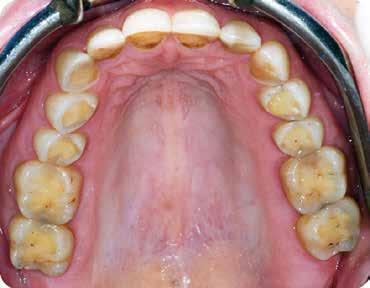

ezen a területen, a fogászat profitál az ilyen fejlesztésekből, és ma már számos kezelési megoldást kínálunk pácienseinknek. Rezidens korom alatt klinikai szakfelügyelőként dolgoztam akadémiai környezetben, ahol elsősorban kivehető fogpótlásra szoruló geriátriai betegeket kezeltem, valamint olyanokat, akiknek fix fogpótlásra, például fog- vagy implantátummal ellátott hagyományos rögzített fogpótlásra (azaz korona és híd) volt szükségük, elsősorban arany vagy fémkerámia felhasználásával. Az ezekben az években megfigyelt klinikai kudarcok és a beavatkozások invazív jellege, nevezetesen a foghúzásra vonatkozó több fúrás és egyszerűbb döntések jelentős szerepet játszottak a kutatási irányvonalam kialakításában az évek során. Ez volt az az időszak is, amikor elkezdtem többet foglalkozni az adhezív fogászattal, ami megváltoztatta a protetikai fogászat klasszikus arculatát, és határozottan kevésbé invazívvá tette azt (1. a-d ábrák). Ma, az intenzív transzlációs és klinikai kutatás eredményeként, különös tekintettel a fogászati bioanyagok alkalmazására, klinikai szakértelmem a minimálisan invazív, adhezív eljárások alkalmazására összpontosít a protetikai fogászatban, a szövődmények kezelésére és a költséghatékony kezelési lehetőségek felkínálására.

1. a-d ábrák: a) Fogerózió a molárisok okkluzális felszínén, b) maratás foszforsavval, c) minimálisan invazív műgyanta-kompozit fedőréteg levegővel történő felszívása, d) adhezív ragasztott fedőréteg a hiányzó zománc és dentin helyreállítására.